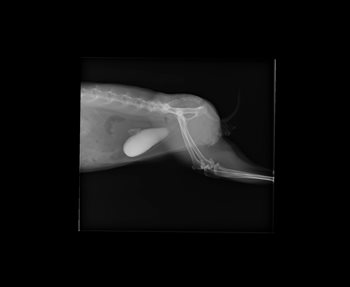

Op de röntgenfoto's is de witte blaas te zien. Dit komt doordat de blaas vol zit met "zand", ook wel calcium-oxalaten genoemd.

Behandeling

We hebben bij dit konijn de blaas tijdens een operatie uitgespoeld: door middel van een katheter zijn de kristallen uit de blaas gehaald. Ook werden er meerdere kleine steentjes gevonden bij dit konijn, waardoor de urineweg verstopt zat. De voeding van het konijn zal moeten worden aangepast (minder biks of ander calcium rijk voer (likstenen)).